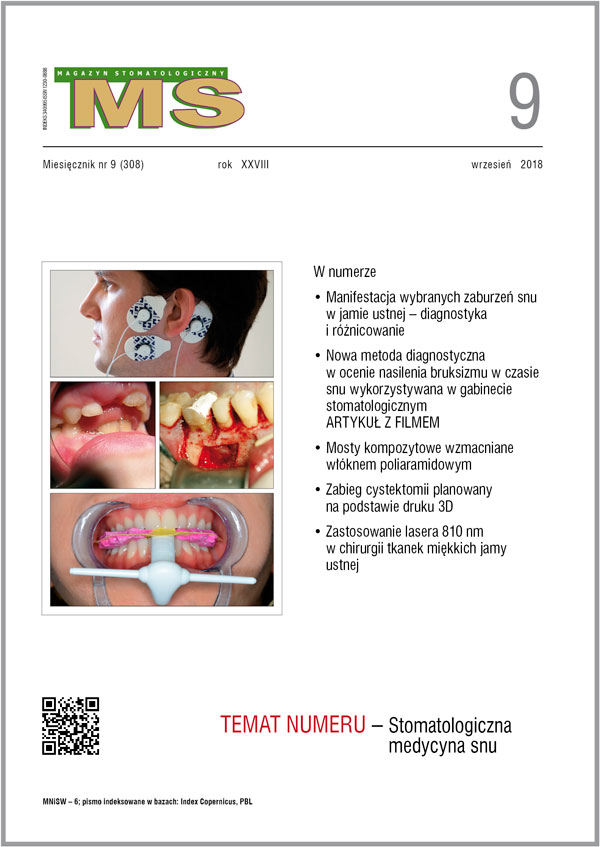

tematem miesiąca wrześniowego numeru „Magazynu Stomatologicznego” jest STOMATOLOGICZNA MEDYCYNA SNU. Dział ten został przygotowany pod przewodnictwem naukowym Pana dr. hab. Mieszka Więckiewicza, kierownika Katedry i Zakładu Stomatologii Doświadczalnej Uniwersytetu Medycznego im. Piastów Śląskich we Wrocławiu. Poza artykułami dotyczącymi diagnostyki i różnicowania patologii snu (bruksizm, bezdech senny) znajdą w nim Państwo także publikację dotyczącą neurobiologicznej koncepcji działania deprogramatorów przednich.

Zachęcam również do zapoznania się z innymi działami naszego czasopisma. W dziale STOMATOLOGIA PRAKTYCZNA zamieściliśmy opisy ciekawych przypadków, w tym przypadek pacjenta z wrodzonym brakiem zawiązków zębów siecznych bocznych szczęki, u którego – po niezadowalającym leczeniu ortodontycznym – wykonano dwa adhezyjne mosty kompozytowe, leczenie endodontyczne zęba siecznego z resorpcją wewnętrzną czy też planowanie, przebieg oraz roczną obserwację zabiegu cystektomii wraz z resekcją korzeni dwóch zębów. Natomiast pod koniec numeru streszczenie ciekawego artykułu z piśmiennictwa, a w VADEMECUM STOMATOLOGA porada specjalisty dotycząca usuwania zębów mlecznych ze wskazań ortodontycznych.